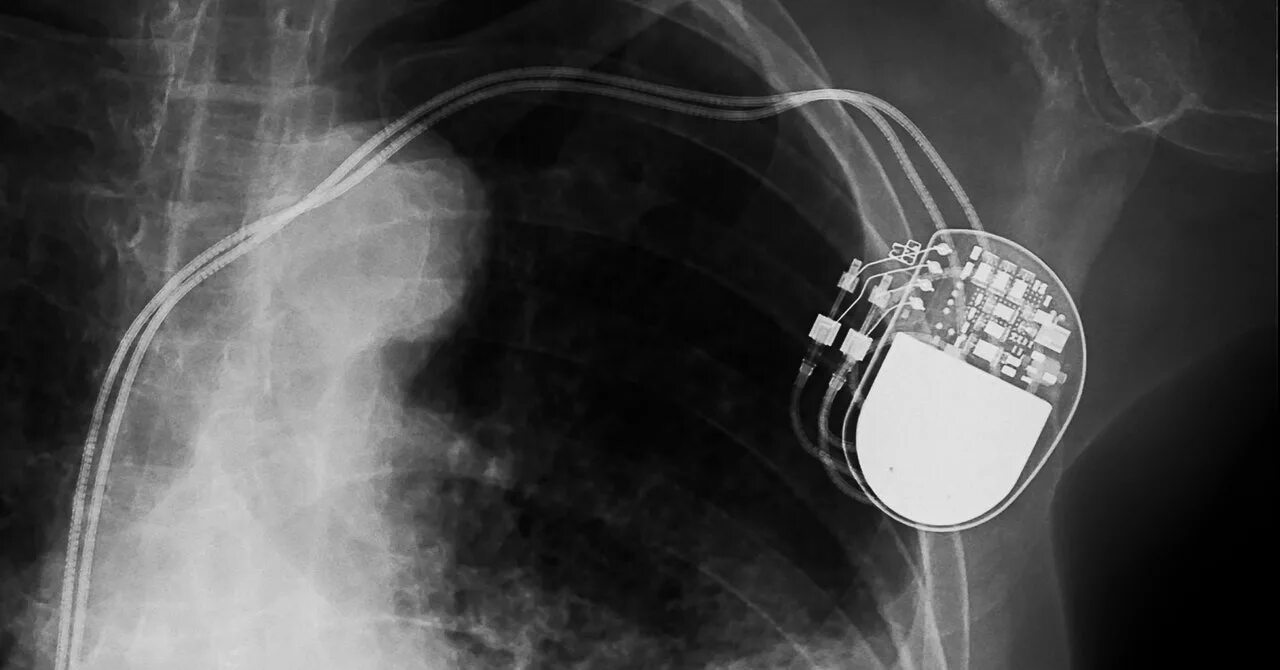

Как делают операцию кардиостимулятор